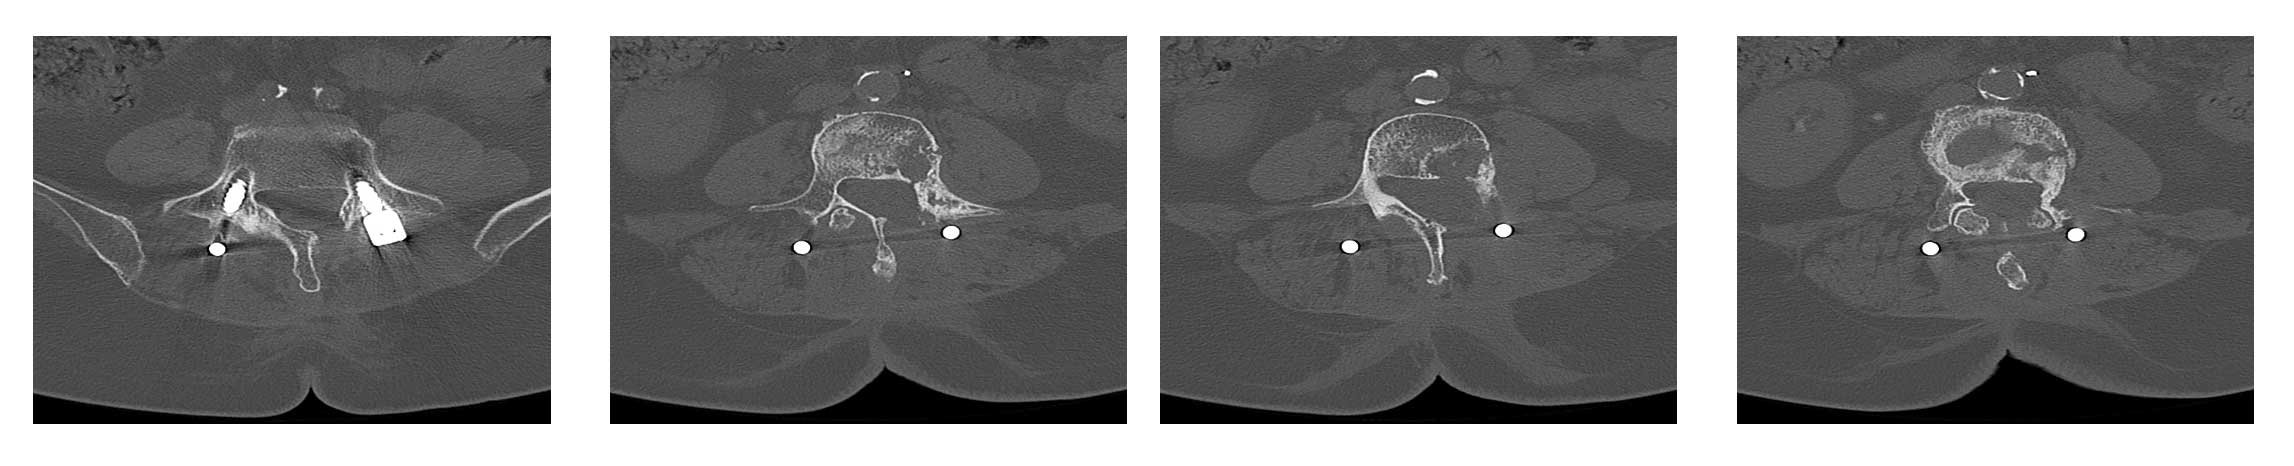

Ameliyat Öncesi: Tomografide vidalarda gevşeme ve omurgada kırığın eşlik ettiği harabiyet görülmekte.